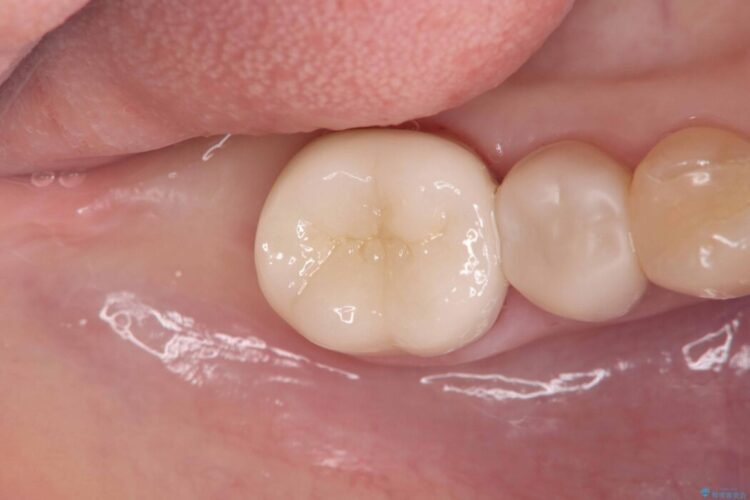

欠けた奥歯をPGAで補強。違和感のない咬み心地へ

欠けた奥歯をPGAで補強。違和感のない咬み心地へ ビフォー 欠けた奥歯をPGAで補強。違和感のない咬み心地へ アフター

以前治療した奥歯(右下7番)の詰め物が欠けてしまったとご来院された患者様です。